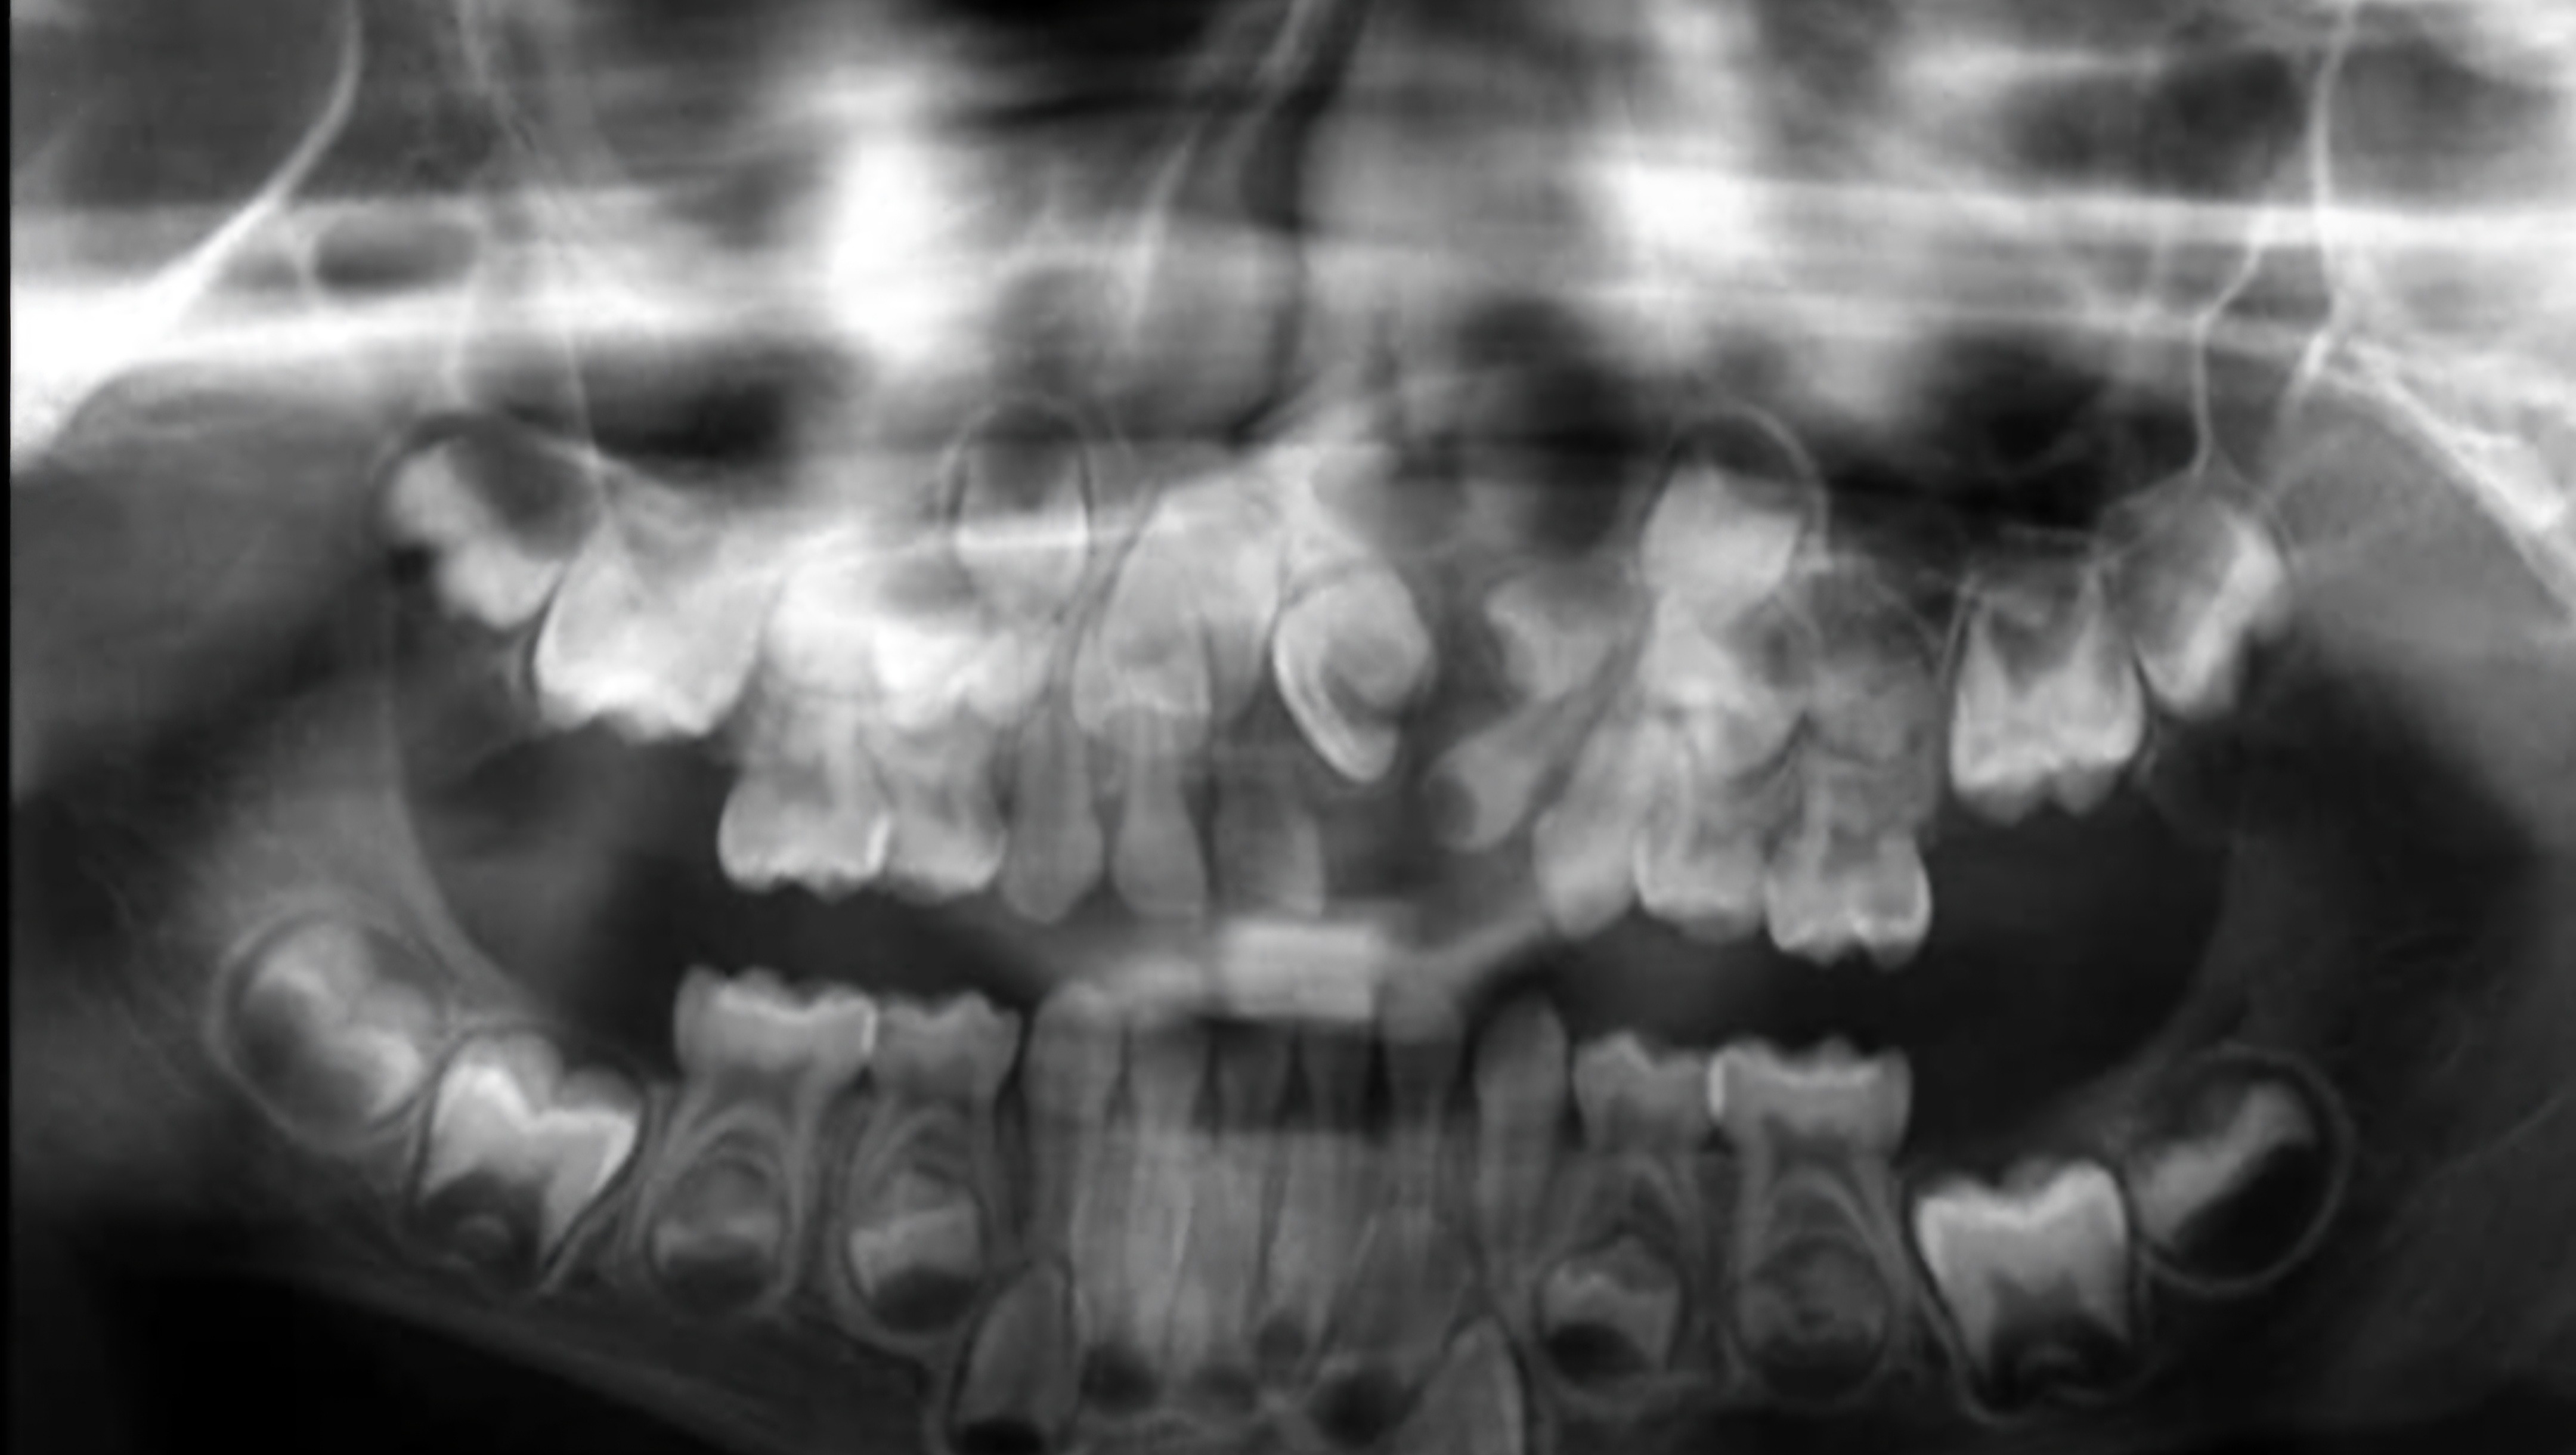

Since birth, Levi endured extensive surgeries starting at 1 month old to correct his cleft palate. He went through another huge palate repair at 14 months old, and another lip revision at the age of 3. In order to do the rest of the needed surgeries, Levi MUST complete extensive phase(s) of Orthodontics before he can proceed with the much needed surgery to correct his palate and repair again and do bone grafts for his gum line.

They were offered monthly payments at this Orthodontist clinic, but struggle to keep up. Scraping pennies has helped them get by with down payments on the extensive treatment needed, before finally receiving his palatal expander. He is Is FINALLY ready for brackets and wires! As a mother, most can agree that they would do anything to give their child a normal smile. His mom is a hard working, loving and dedicated person who I've known almost my entire life, and God has put it on my heart to try to help take this burden from her shoulders. I have included a picture of the payment plan, with the price of phase 1 treatment. They have exhausted everything that they have into everything needed, to get to now! I would love to raise the money needed for phase 1 of treatment, and put down the down-payment for phase 2. This would be life changing for them to take this burden from their shoulders! Every single penny will be handed to the Orthodontist for treatment.